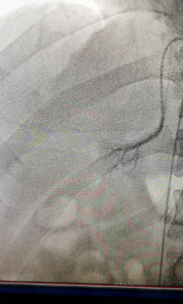

?——我院成功開展雙側(cè)腎上腺靜脈插管采血術(shù)?近日,我院心內(nèi)科、檢驗(yàn)科、內(nèi)分泌科、泌尿外科多科協(xié)作,成功開展了雙側(cè)腎上腺靜脈插管采血術(shù)。該項(xiàng)高血壓診療新技術(shù)目前只在國(guó)內(nèi)少部分醫(yī)院開展。我院首次開展此項(xiàng)技術(shù)后,明確了患者高血壓的病因,實(shí)現(xiàn)了高血壓的精準(zhǔn)治療,標(biāo)志著該院對(duì)高血壓的診治水平提高到了一個(gè)新的臺(tái)...